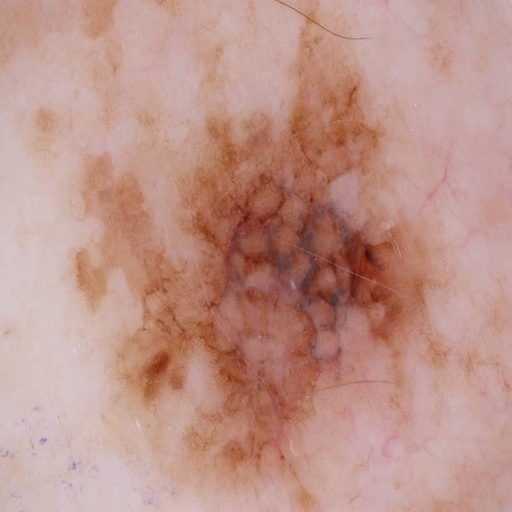

A Survey on Deep Learning for Skin Lesion Segmentation

Kumar Abhishek*, Zahra Mirikharaji*, Alceu Bissoto, Catarina Barata, Sandra Avila, Eduardo Valle, M. Emre Celebi, Ghassan Hamarneh [*: Joint first authors]

Medical Image Analysis, 2023 We review the literature on deep learning-based skin lesion segmentation, evaluating the current research along several dimensions: input data, model design, and evaluation, and discuss their limitations and potential research directions. [Abstract] [BibTeX] [Interactive Table of Papers]

Skin cancer is a major public health problem that could benefit from computer-aided diagnosis to reduce the burden of this common disease. Skin lesion segmentation from images is an important step toward achieving this goal. However, the presence ofnatural and artificial artifacts (e.g., hair and air bubbles), intrinsic factors (e.g., lesion shape and contrast), and variations in image acquisition conditions make skin lesion segmentation a challenging task. Recently, various researchers have explored the applicability of deep learning models to skin lesion segmentation. In this survey, we cross-examine 177 research papers that deal with deep learning-based segmentation of skin lesions. We analyze these works along several dimensions, including input data (datasets, preprocessing, and synthetic data generation), model design (architecture, modules, and losses), and evaluation aspects (data annotation requirements and segmentation performance). We discuss these dimensions both from the viewpoint of select seminal works, and from a systematic viewpoint, examining how those choices have influenced current trends, and how their limitations should be addressed. To facilitate comparisons, we summarize all examined works in a comprehensive table as well as an interactive table available online.

Matthews Correlation Coefficient Loss for Deep Convolutional Networks: Application to Skin Lesion Segmentation

Kumar Abhishek, Ghassan Hamarneh

International Symposium on Biomedical Imaging (ISBI), 2021 We propose a new overlap-based loss function for binary segmentation that takes into account the true negative pixels and achieves a better sensitivity-specificity trade-off than the popular Dice loss. [Abstract] [BibTeX] [Poster]

The segmentation of skin lesions is a crucial task in clinical decision support systems for the computer aided diagnosis of skin lesions. Although deep learning-based approaches have improved segmentation performance, these models are often susceptible to class imbalance in the data, particularly, the fraction of the image occupied by the background healthy skin. Despite variations of the popular Dice loss function being proposed to tackle the class imbalance problem, the Dice loss formulation does not penalize misclassifications of the background pixels. We propose a novel metric-based loss function using the Matthews correlation coefficient, a metric that has been shown to be efficient in scenarios with skewed class distributions, and use it to optimize deep segmentation models. Evaluations on three skin lesion image datasets: the ISBI ISIC 2017 Skin Lesion Segmentation Challenge dataset, the DermoFit Image Library, and the PH2 dataset, show that models trained using the proposed loss function outperform those trained using Dice loss by 11.25%, 4.87%, and 0.76% respectively in the mean Jaccard index. The code is available on GitHub.

Illumination-based Transformations Improve Skin Lesion Segmentation in Dermoscopic Images

Kumar Abhishek, Ghassan Hamarneh, Mark S. Drew

ISIC Skin Image Analysis Workshop, IEEE International Conference on Computer Vision and Pattern Recognition (CVPR), 2020 We incorporate information from specific color bands, illumination invariant grayscale images, and shading-attenuated images obtained from RGB dermoscopic images of skin lesions to improve the lesion segmentation. [Abstract] [BibTeX] [Presentation Slides]

The semantic segmentation of skin lesions is an important and common initial task in the computer aided diagnosis of dermoscopic images. Although deep learning-based approaches have considerably improved the segmentation accuracy, there is still room for improvement by addressing the major challenges, such as variations in lesion shape, size, color and varying levels of contrast. In this work, we propose the first deep semantic segmentation framework for dermoscopic images which incorporates, along with the original RGB images, information extracted using the physics of skin illumination and imaging. In particular, we incorporate information from specific color bands, illumination invariant grayscale images, and shading-attenuated images. We evaluate our method on three datasets: the ISBI ISIC 2017 Skin Lesion Segmentation Challenge dataset, the DermoFit Image Library, and the PH2 dataset and observe improvements of 12.02%, 4.30%, and 8.86% respectively in the mean Jaccard index over a baseline model trained only with RGB images.

Mask2Lesion: Mask-Constrained Adversarial Skin Lesion Image Synthesis

Kumar Abhishek, Ghassan Hamarneh

Workshop on Simulation and Synthesis in Medical Imaging (SASHIMI), International Conference on Medical Image Computing and Computer Assisted Intervention (MICCAI), 2019 We propose a GAN-based synthesis approach for generating realistic skin lesion images from lesion masks, making it an appropriate augmentation strategy for skin lesion segmentation datasets. [Abstract] [BibTeX] [Poster]

Skin lesion segmentation is a vital task in skin cancer diagnosis and further treatment. Although deep learning based approaches have significantly improved the segmentation accuracy, these algorithms are still reliant on having a large enough dataset in order to achieve adequate results. Inspired by the immense success of generative adversarial networks (GANs), we propose a GAN-based augmentation of the original dataset in order to improve the segmentation performance. In particular, we use the segmentation masks available in the training dataset to train the Mask2Lesion model, and use the model to generate new lesion images given any arbitrary mask, which are then used to augment the original training dataset. We test Mask2Lesion augmentation on the ISBI ISIC 2017 Skin Lesion Segmentation Challenge dataset and achieve an improvement of 5.17% in the mean Dice score as compared to a model trained with only classical data augmentation techniques.